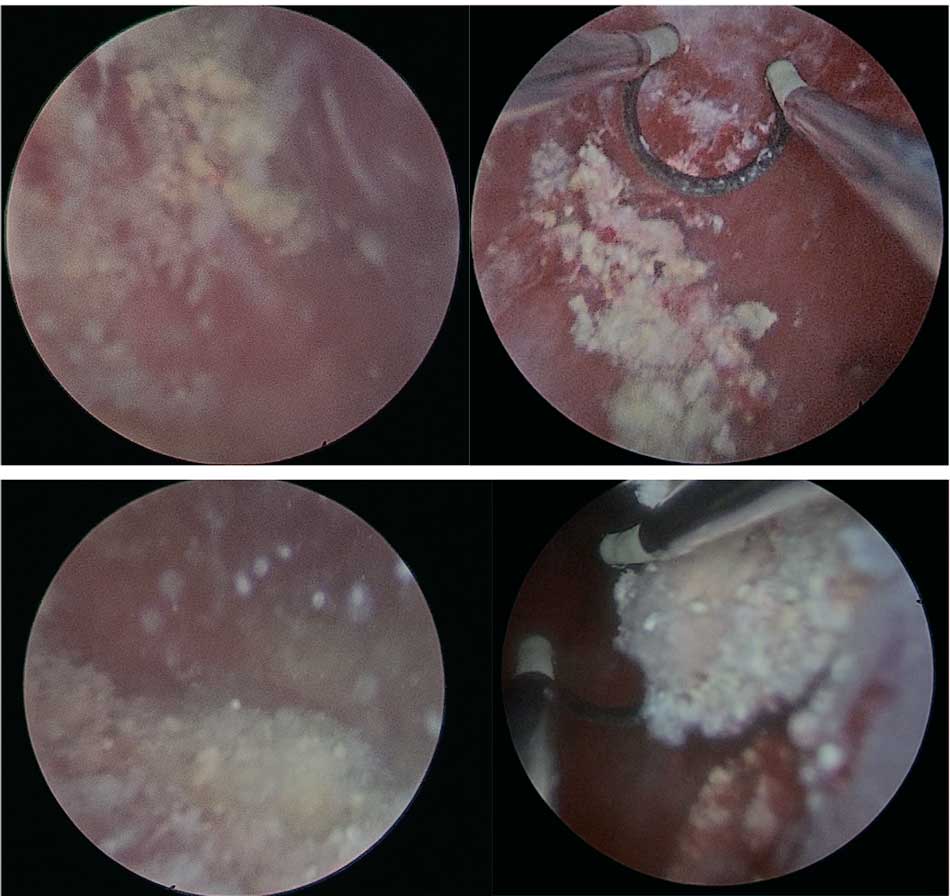

При цистоскопии у всех пациентов была выявлена гиперемия слизистой с эрозированными участками, множественные конкременты, фиксированные к стенке мочевого пузыря и свободно перемещающиеся в полости мочевого пузыря. При этом емкость мочевого пузыря у всех пациентов была достаточная – 200,0±46,0 мл (рис. 3, 4).

Рис. 3. Цистоскопическая картина инкрустирующего цистита

Fig. 3. Cystoscopic picture of encrusting cystitis

Рис. 4. Удаленные конкременты из просвета мочевого пузыря при инкрустирующем цистите

Fig. 4. Removed concretions from the lumen of the bladder in case of encrusting cystitis